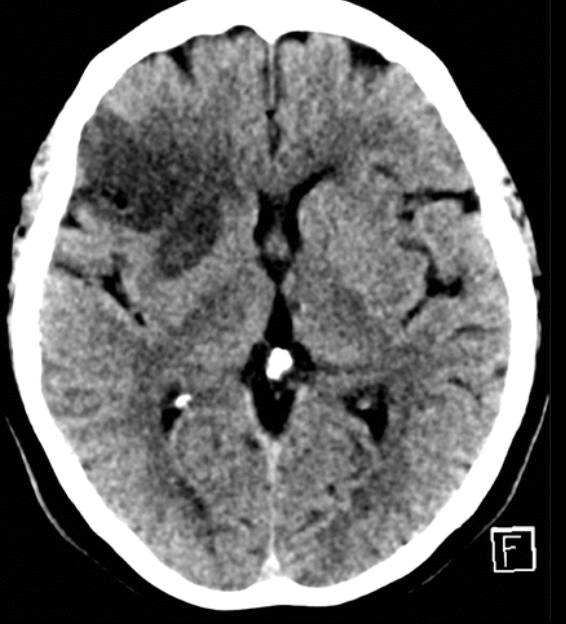

EVC isquémico

Fase hiperaguda